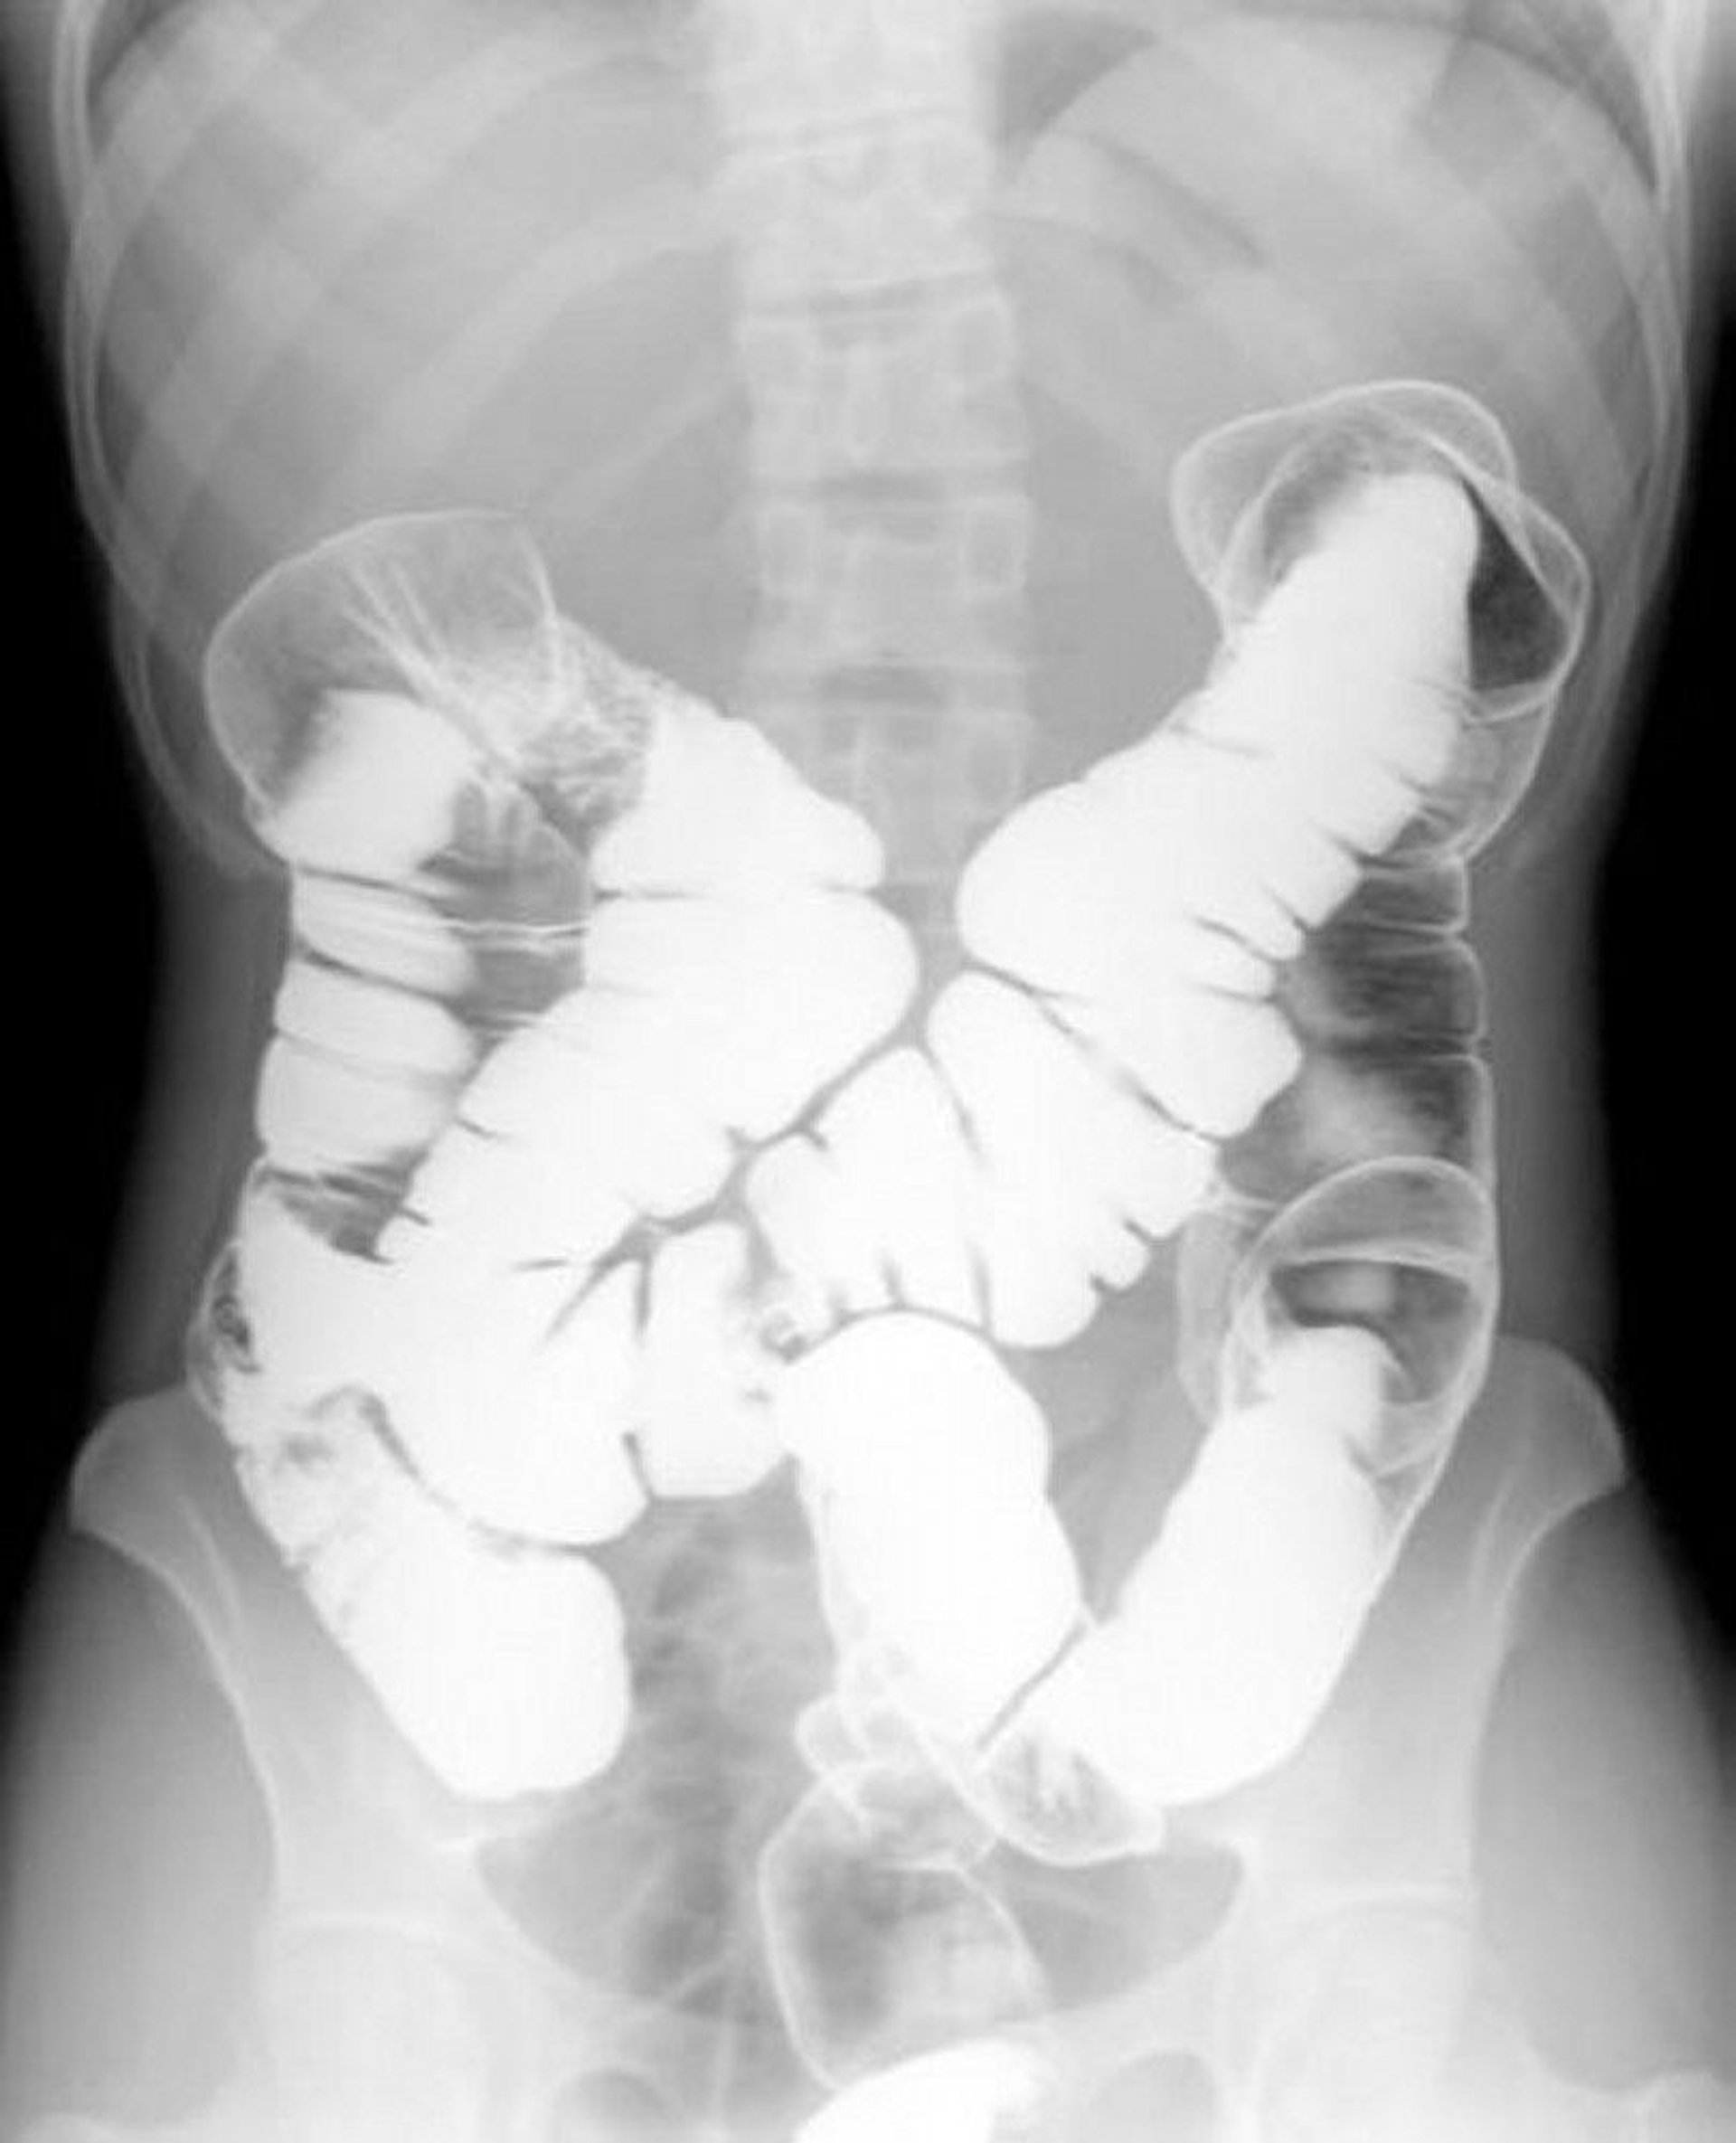

Double-Contrast Barium Enema Showing Normal Anatomy

This image shows the pattern of air and barium within a normal colon.